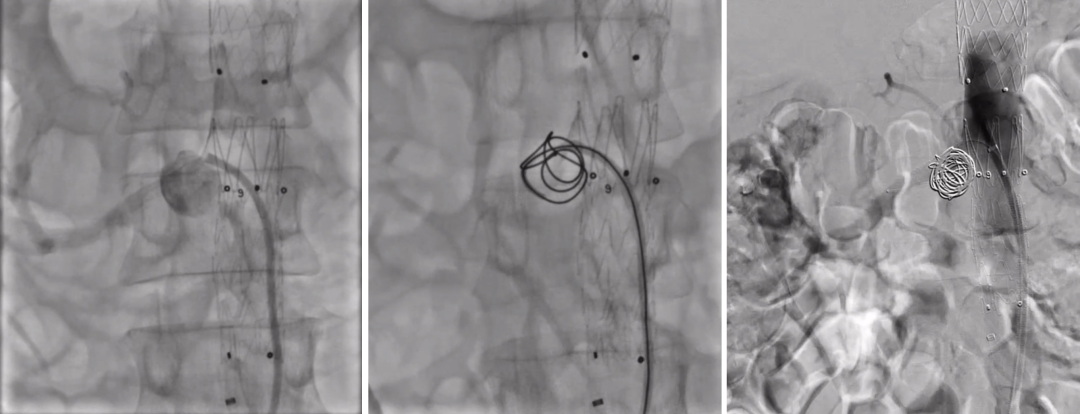

RDC Guiding配合导管Interlock-35 20mm×40cm;Interlock-18 14mm×30cm可控弹簧圈栓塞右肾动脉瘤;

右肾动脉内植入Viabahn 7mm×25mm,超出主动脉内5mm释放

造影,封堵穿刺点,术毕。

术后造影